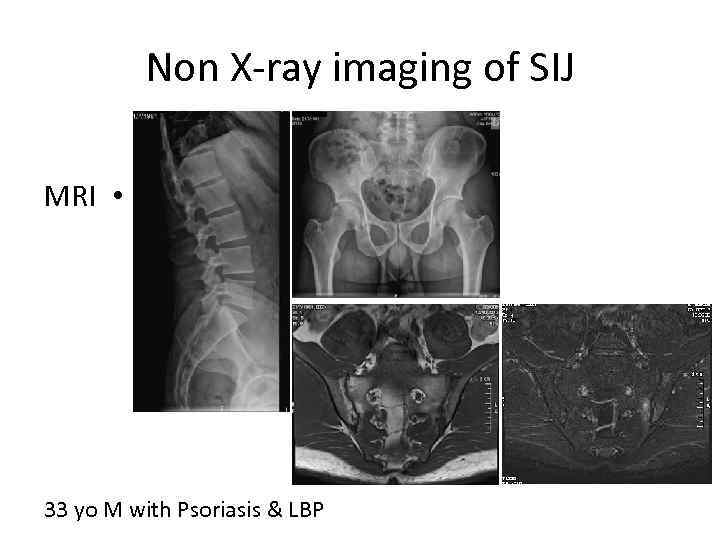

Non X-ray imaging of SIJ MRI • 33 yo M with Psoriasis & LBP